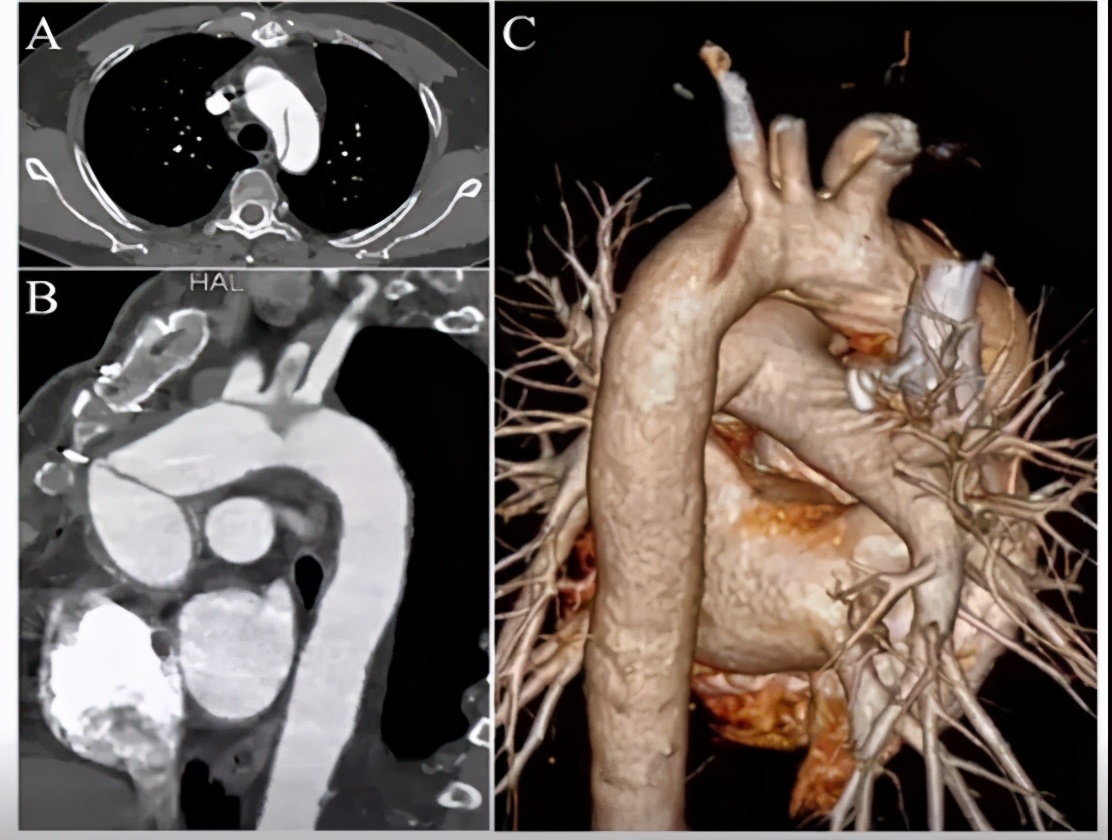

手术方法:弓上三分支预开窗+内分支+主动脉腔内修复术。

手术步骤:弓上分支体外预开窗+内分支缝合;释放远端限制支架+近端主体支架;弓上分支支架植入。

手术关注点:弓部动脉瘤原位开窗操作难度大,术中存在较大风险;而如果使用烟囱支架,则内漏风险大。所以,决定行预开窗+体外缝制内分支,增加重建弓上分支成功率,降低术中缺血风险、内漏风险。